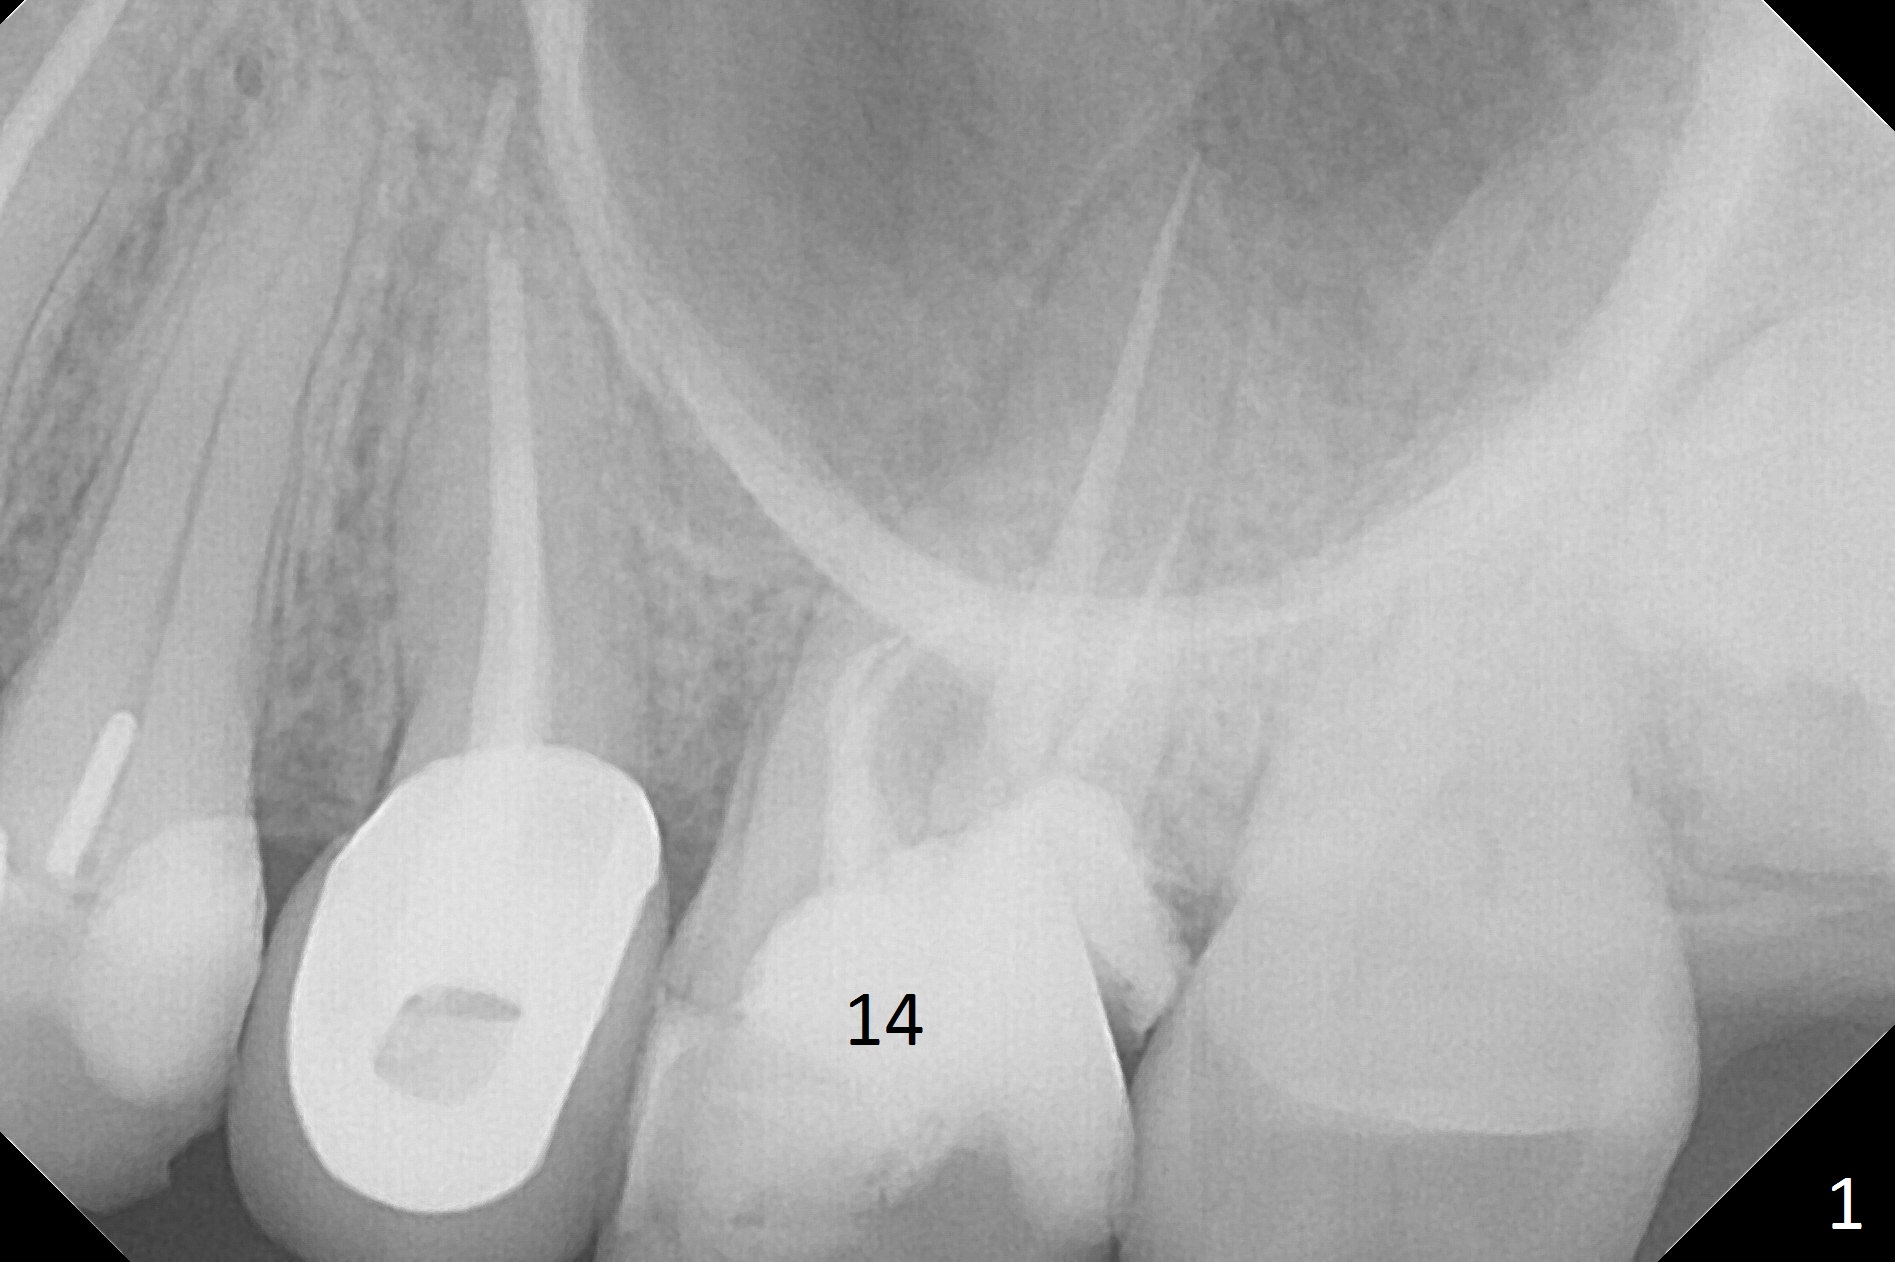

A 61-year-old woman has pain after RCT at #14 (Fig.1). Exam shows subgingival crack. After difficult extraction, allograft with Osteogen is placed in the 3 sockets, followed by Osteogen plug and 4-0 Chromic Gut Suture. The distal gingiva appears to be migrating into the center of the sockets (Fig.2 arrow). Due to insurance issue, an implant will be placed early next year. The patient returns 9 months post extraction (Fig.3). If the ridge proves to be not so wide, make incision, start osteotomy with 1.6 mm pilot drill, followed by 4.3 mm Magic Drill for 7 mm and 3.8 mm Magic Expander for another 2 mm (sinus lift, BEB, Fig.4). Otherwise start Magic Split. If the bone is dense, use drills and Expander as mentioned above with the depths 2 mm more (Fig.5), followed by Magicore. The tissue-level implant improves the crown/implant ratio over the FC. After socket healing, gingival cuff height is stable. The cuff of Magicore is easy to determine vs. immediate case.